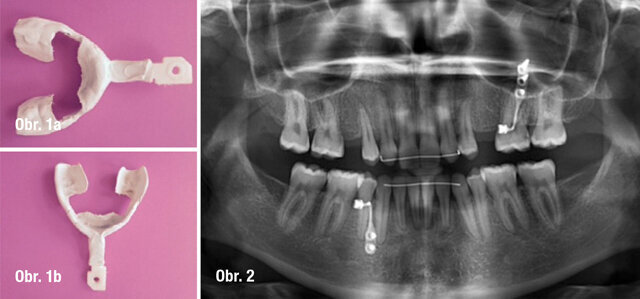

NaviStent chirurgická dlaha, Předoperační panoramatický RTG snímek

Před zákrokem byl sejmut otisk zubního oblouku pomocí ireverzibilního hydrokoloidu (Cavex CA37, fast set, CavexHolland) pro výrobu studijního modelu. Tento model byl použit pro výrobu chirurgické dlahy, dále jen NaviStent (obr. 1a, b). NaviStent sloužila jako skenovací šablona a byla také použita v průběhu chirurgického zákroku. Poté byla pacientka odeslána s nasazenou NaviStent na vyšetření CBCT (obr. 2; 3a, b; 4a, b).